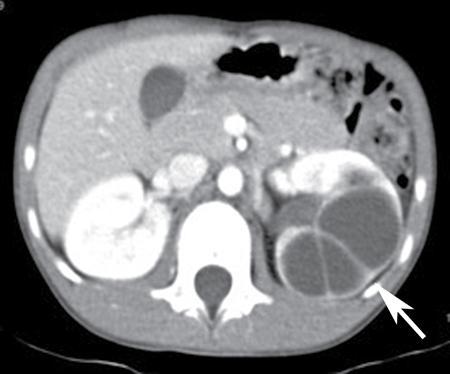

- Renal sinus cysts are simple cysts that are present within renal sinus. It includes two distinct entity, namely, parapelvic cyst and peripelvic cyst. Parapelvic cyst is simple renal cyst that arises from medial renal parenchyma, and extends into renal pelvic sinus. These are usually asymptomatic. Sometimes, they can compress on renal pelvis or vasculature to cause hydronephrosis, hypertension or haematuria. Second entity is peripelvic cyst, which are benign extraparenchymal cysts that are located in renal sinus, and are thought to be of lymphatic origin. They are rarely symptomatic (Fig. 10.12.1.2).

- Renal sinus cyst could mimic hydronephrosis, that can be differentiated on excretory phase of CT urography, as these cysts do not show contrast opacification in excretory phase.